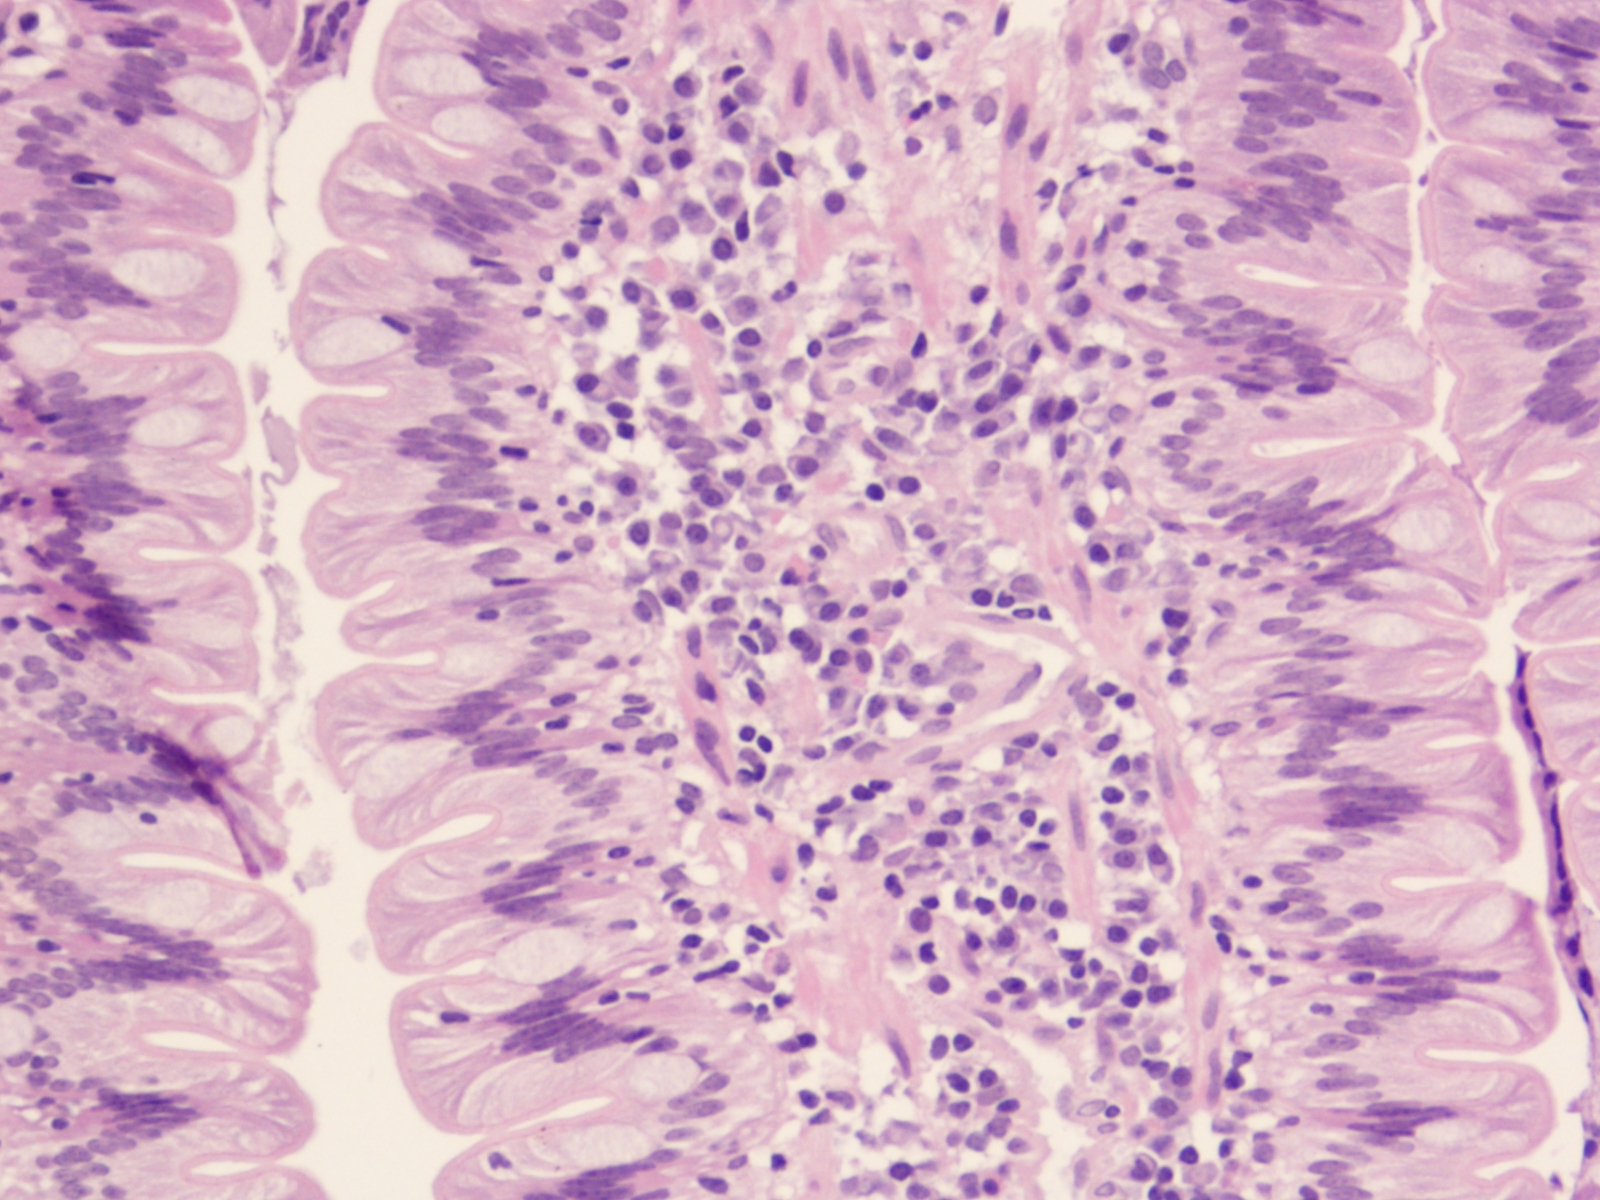

HE-kleuring van een coupe van de maag mucosa ter hoogte van de fundus (400 x). Aan de rechterzijde van de foto bevindt zich een gedeelte vande bedekkende epitheellaag, bedekt door slijm. In dit slijm bevinden zich karakteristieke helix-achtige bacteriën, die herkend worden als Helicobacter spp. De aanwezigheid van deze bacteriën worden frequent geassocieerd met maagdarmklachten (1). Bij de kat wordt een chronische infectie met Helicobacter heilmannii in verband gebracht met de ontwikkeling van een grootcellig B-cel lymfoom in de maag.

HE-gekleurde coupe van een darmvlok in het duodenum. De lamina propria bevat aanzienlijke aantallen gedifferentieerde lymfocyten en vooral plasmacellen, passend bij een lymfo-plasmacellulaire enteritis (200 x).